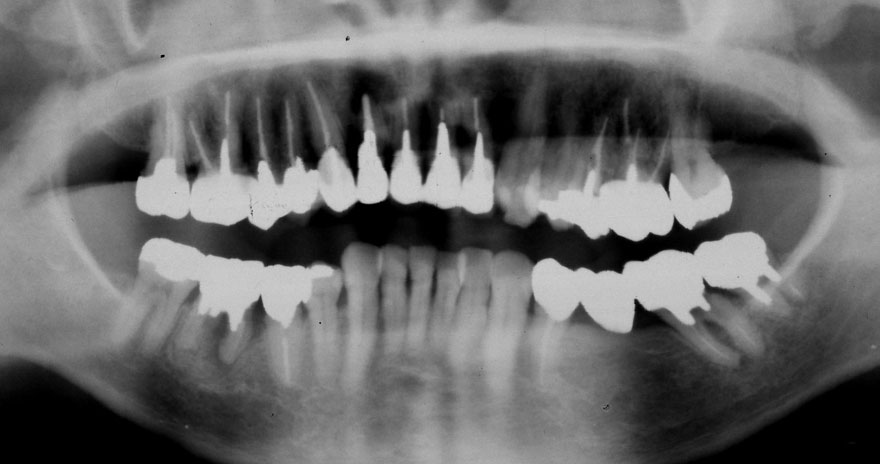

初診時 39歳 女性 平均歯槽骨喪失量:1.82mm

29年後 68歳

平均歯槽骨喪失量:2.21mm

29年間喪失量:-0.39mm

年間喪失速度:-0.013mm

(ケア頻度:5.55ヵ月ごと)